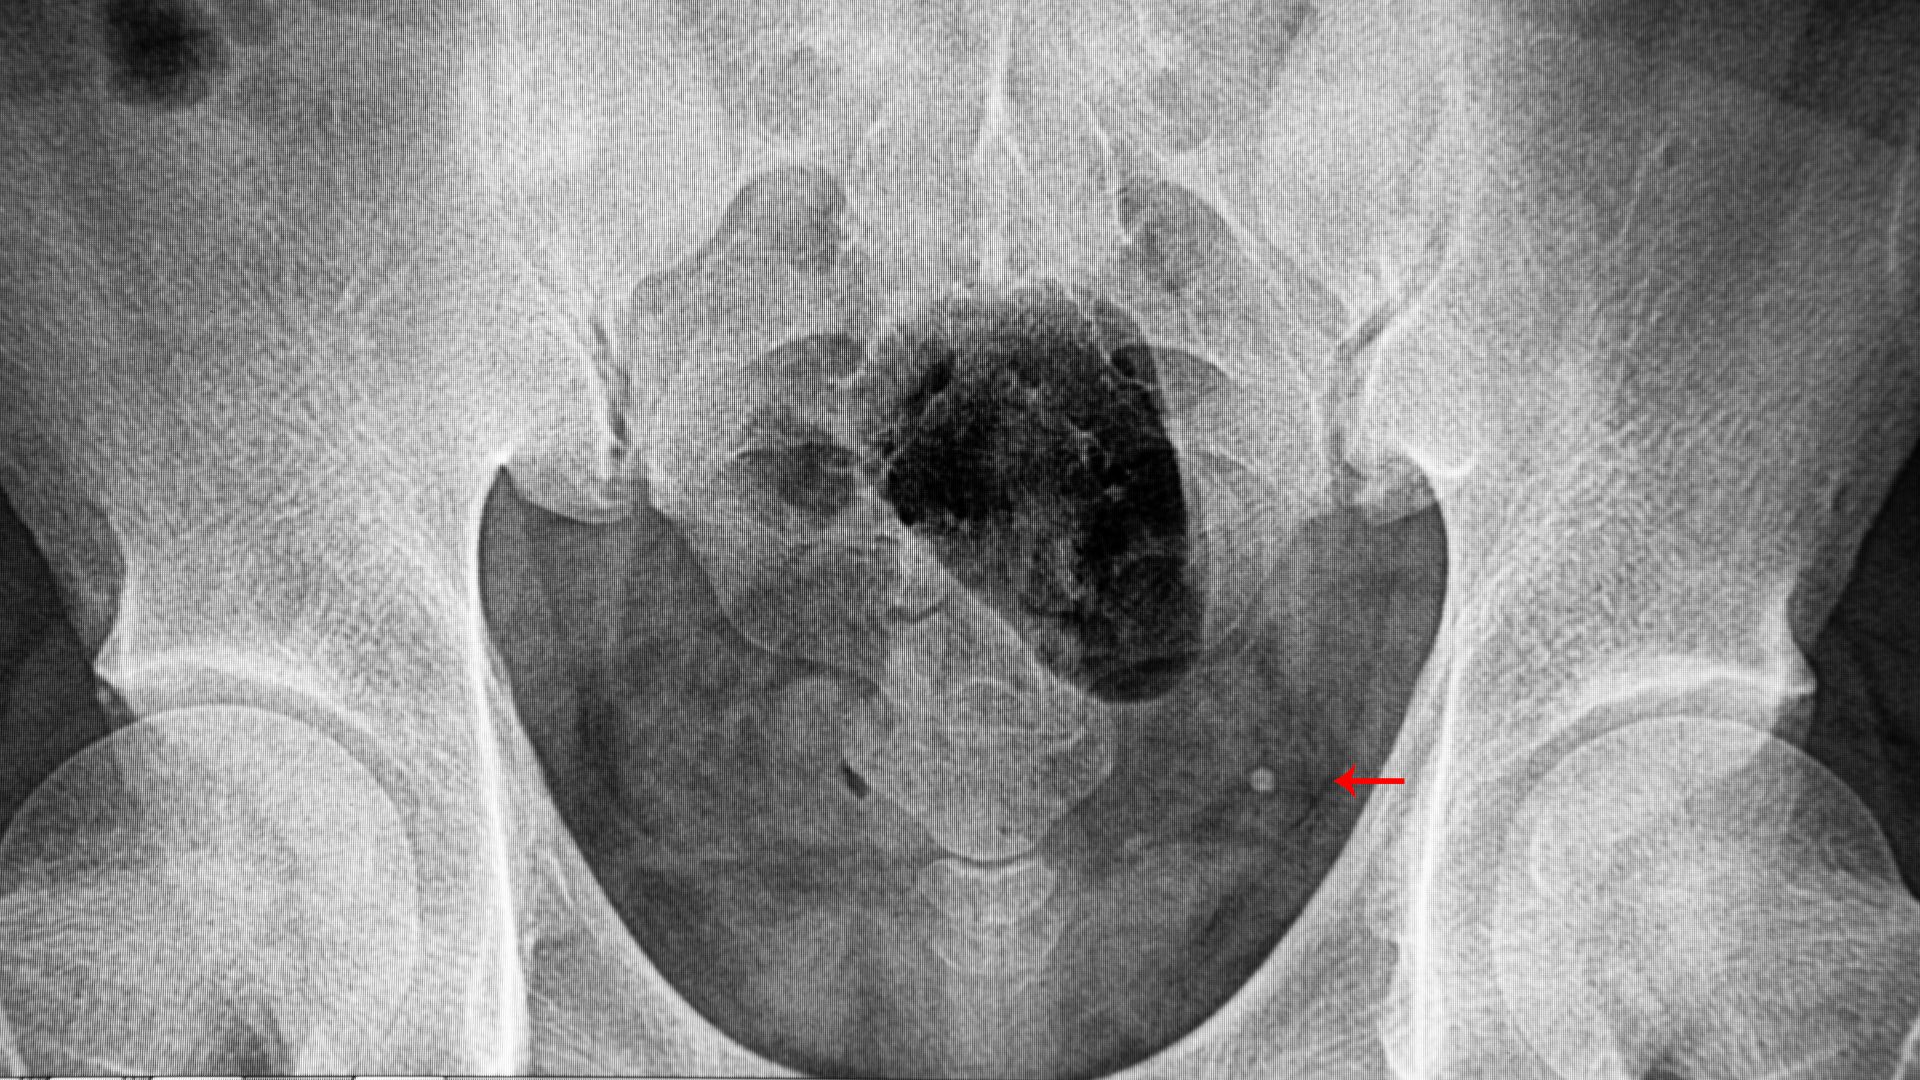

- Chụp CT hệ tiết niệu: Xác định rõ vị trí hẹp và nguyên nhân như sỏi, khối u.

- Chụp niệu đồ hoặc nội soi niệu quản: Quan sát trực tiếp lòng niệu quản, giúp đánh giá chính xác đoạn hẹp và hỗ trợ điều trị.